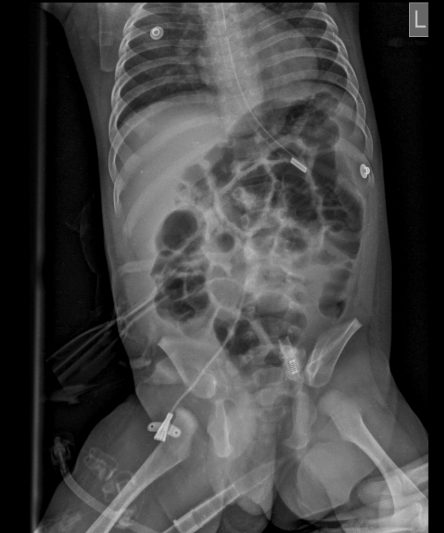

Microskan with Ultra high frequency can take the Lateral Lumbar Spine image of a 90 kg Patient with the correct image receptor